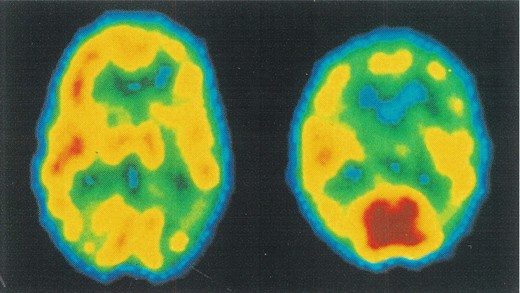

Sol taraftaki görüntülemede sağlıklı kişinin beyninde metabolizma hızının dağılımını görüyorsunuz, eşit ve uyumlu. Sağda şizofren bir kişinin beyninde oksijen ve glikoz tüketiminin nasıl uygunsuz olduğu görülüyor. Koyu kırmızı olarak görüntülenen beyin bölgesi yoğun aktivite gösteriyor. Bu bölge hayal kurma ile ilgili ve beyin bütünlüğünden kopuk çalışıyor. Son Nörogörüntüleme teknikler, (PET) Şizofren kişinin dünyadan kopuk yaşantısının beyinsel karşılığı olarak çarpıcı bilgiler veriyor.

Şizofreni beyindeki hücre faaliyetleriyle ilgili bir durumdur. Beynin karar mekanizması, enerji programlaması bozulur. Beynin önem ve önceliklerini belirlemesi, hayal ile gerçek arasındaki sınırları fark etmesi, doğru ve yanlış diye oluşturduğumuz standartların bozulması durumunda şizofreni ortaya çıkar. Bu kişilerde sosyal uyumsuzluk olduğu için üretemezler, sosyalleşemezler, evlenemezler, çocuk sahibi olamazlar, para kazanamazlar.

Bu tür hastaların sayısı sınırlı kalmadığı takdirde bunların sayısı artar ve bir iki nesil sonra insanlık biter. Bu nedenle şizofreni marazi bir durumdur ve tedavi edilmesi gerekir. Beyindeki çalışmalar anlaşıldıkça, algılamalar düzeltildikçe, bu hastalık da tedavi edilir. Bugün ileri beyin görüntüleme yöntemleri ile hastalık tanısı kolaylaşmıştır ve yeni tedavilerde tıp oldukça başarılıdır.